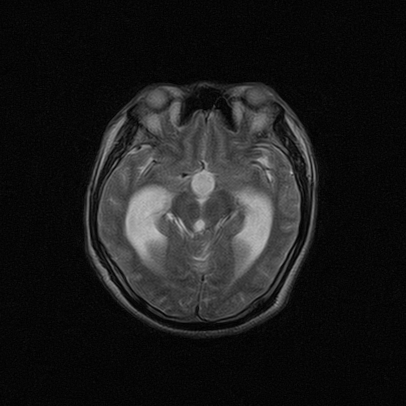

标题: MRI2064:少见病例。男性52,视力下降多年。 [打印本页]

标题: MRI2064:少见病例。男性52,视力下降多年。

四脑室区见混杂信号占位影,脑室系统扩张明显,临近结构显著受压称位,患者52岁,多考虑室管膜瘤可能性大

考虑第四脑室室管膜瘤并阻塞性脑积水。

比较典型的脉络丛乳头状瘤并脑积水,鉴别小脑蚓部血管母细胞瘤。